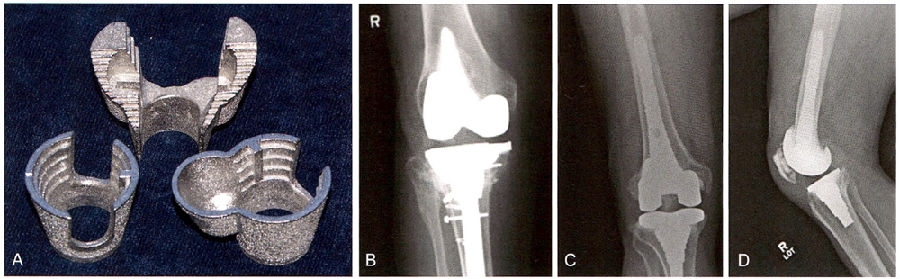

4 用于加强股骨和胫骨的组配式楔形模块

尽管目前在初次置换中常常作为非必要部分多孔金属加强块和锥形袖套的报道应用的效果较好(图5A)。把锥形袖套压配到股骨远端或胫骨近端的包容性骨缺损中,并用骨水泥把假体粘贴于这些加强块上使其成为一体。还可以把锥形袖套和假体组合形成一体式的假体结构。包容性骨缺损中,锥形袖套也可以粘在假体上组合形成单一假体结构。诸如图5BC。这些方法大部分应用于伴有明显骨缺损的翻修手术中。这些锥形袖套的骨整合能力非常好,甚至假体失败后也很难取出。

5 A.将多孔金属锥体放置在干骺端缺损处,以加强固定。B.X线片示用双叶胫骨假体扩大由于胫骨平台骨折不愈合造成的缺损。C.如图所示,类风湿关节炎骨不良患者翻修TKA的正侧位片中,与植入物茎端相连的袖套型假体可以增强骺端包容或非包容性的缺损